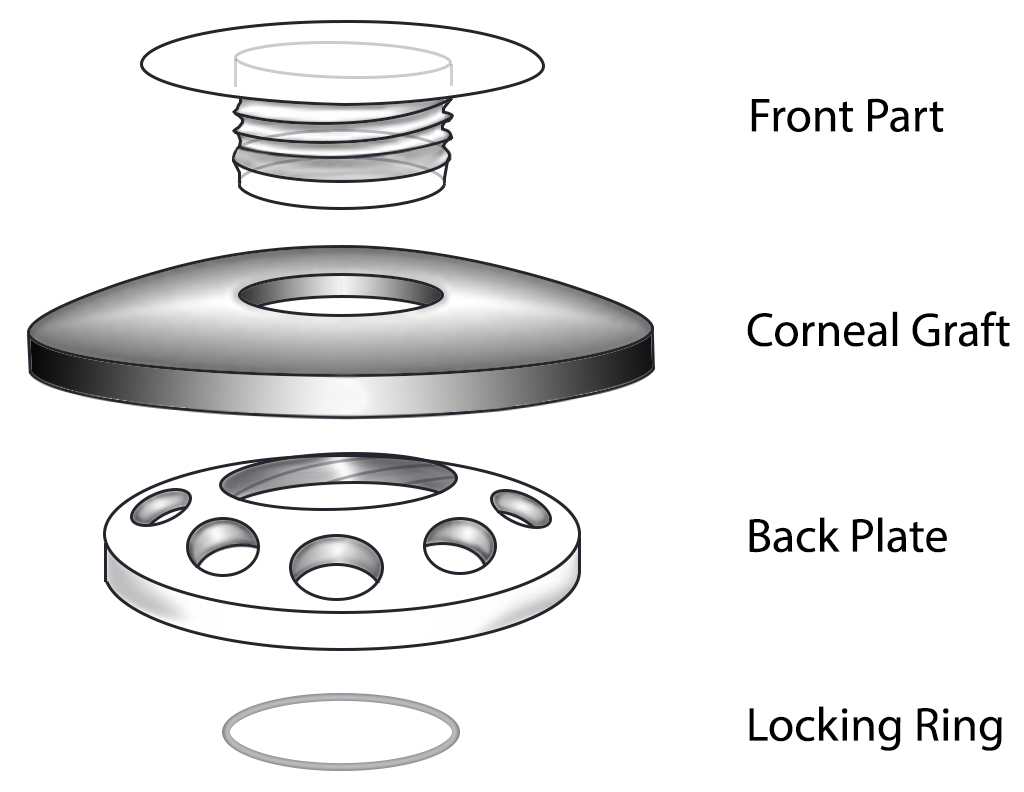

Keratoprosthesis, the transplantation of an artificial cornea, was first performed in Italy by Benedetto Strampelli the 1960s (1). Patients requiring repeat corneal transplantation highlighted the need for an alternative to corneal allograft treatment, as graft survival rates drop with each additional procedure. Historical options have included the osteo-odonto-keratoprosthesis (OOKP) and AlphaCor artificial cornea. These have since been largely replaced by the Boston Type I Keratoprosthesis (KPro), which became approved for use by the U.S. Food and Drug Administration in 1992 (1, 13). The device consists of a clear plastic optic and a prosthetic plate that are sandwiched around a donor allograft or the patient's own corneal tissue. The device is then sutured onto the recipient eye to replace a failed graft or the native cornea. Keratoprosthesis surgery is a procedure of last-resort, reserved for patients who are not candidates for other types of keratoplasty.

Keratoprosthesis implantation is a procedure that involves full-thickness removal of the cornea and replacement by an artificial cornea. The Boston Type I Keratoprosthesis is currently the most commonly used keratoprosthesis device in the US. It consists of a clear plastic polymethylmethacrylate (PMMA) optic and back plate sandwiched around a corneal graft and secured with a titanium locking ring (Figure 15). After the device is assembled, a partial-thickness trephination is performed on the host cornea. Full-thickness resection of the patient's cornea is then completed using curved corneal scissors. The keratoprosthesis is then secured to host tissue using interrupted or running sutures. Generally, patients who have a history of multiple failed PKs are candidates for a keratoprosthesis transplant. Other indications include severe keratitis or ocular surface disease resulting from limbal stem cell failure, such as Stevens-Johnson syndrome (Figure 16), ocular cicatricial pemphigoid, aniridia (Figure 17) and chemical injury (1, 13). The Boston Type II Keratoprosthesis is a similar device with a longer optic designed to extend through an opening made in the upper eyelid (Figure 19). It is indicated for the most severe cicatrizing ocular surface diseases.